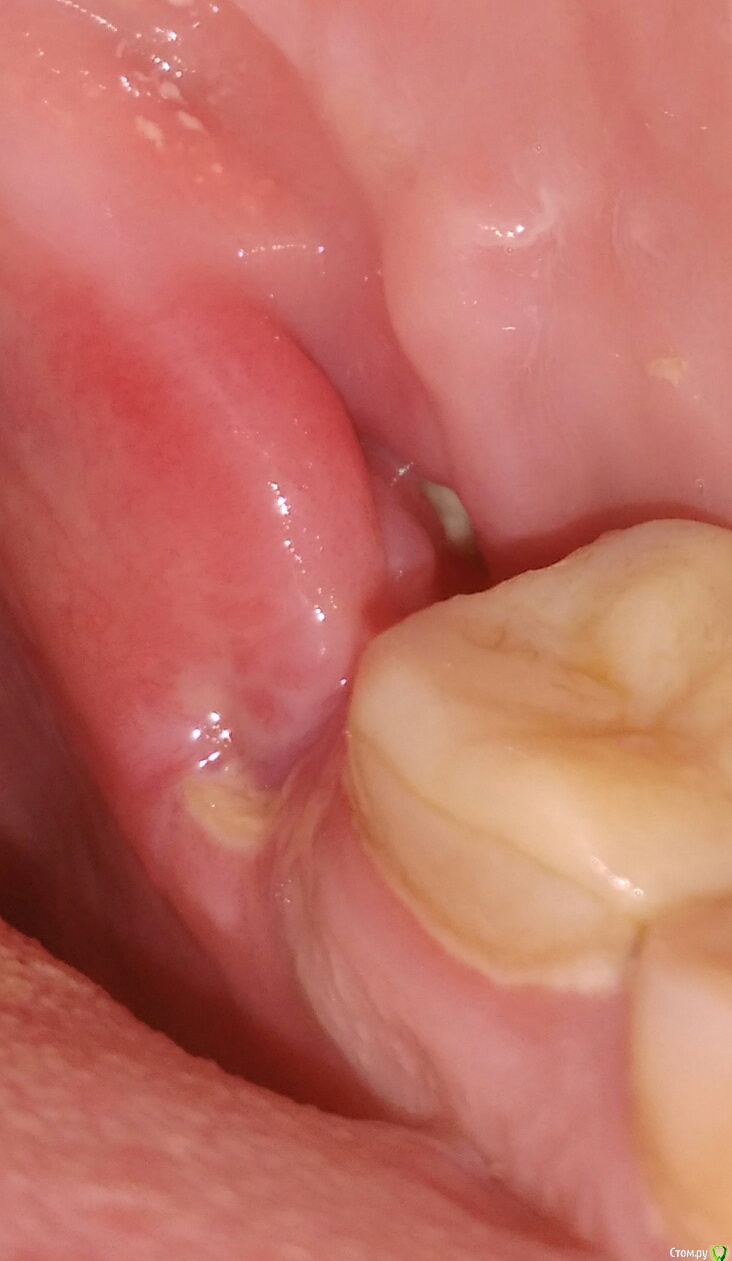

Больше беспокоит оголенный костный "дефект" снизу.

Его врач "подточил" бормашиной, повторно наложил шов.

Шов продержался 8 дней, до 4 сентября, после отхождения шва костный край остался оголенным, т.е.дефект не зарос.

Прошу посоветовать, что с ним делать-то?   Может подождать, или спилено недостаточно, еще пилить?   Врач удалявший рекомендует prp-терапию для заживления.

Фото на текущий момент выложу